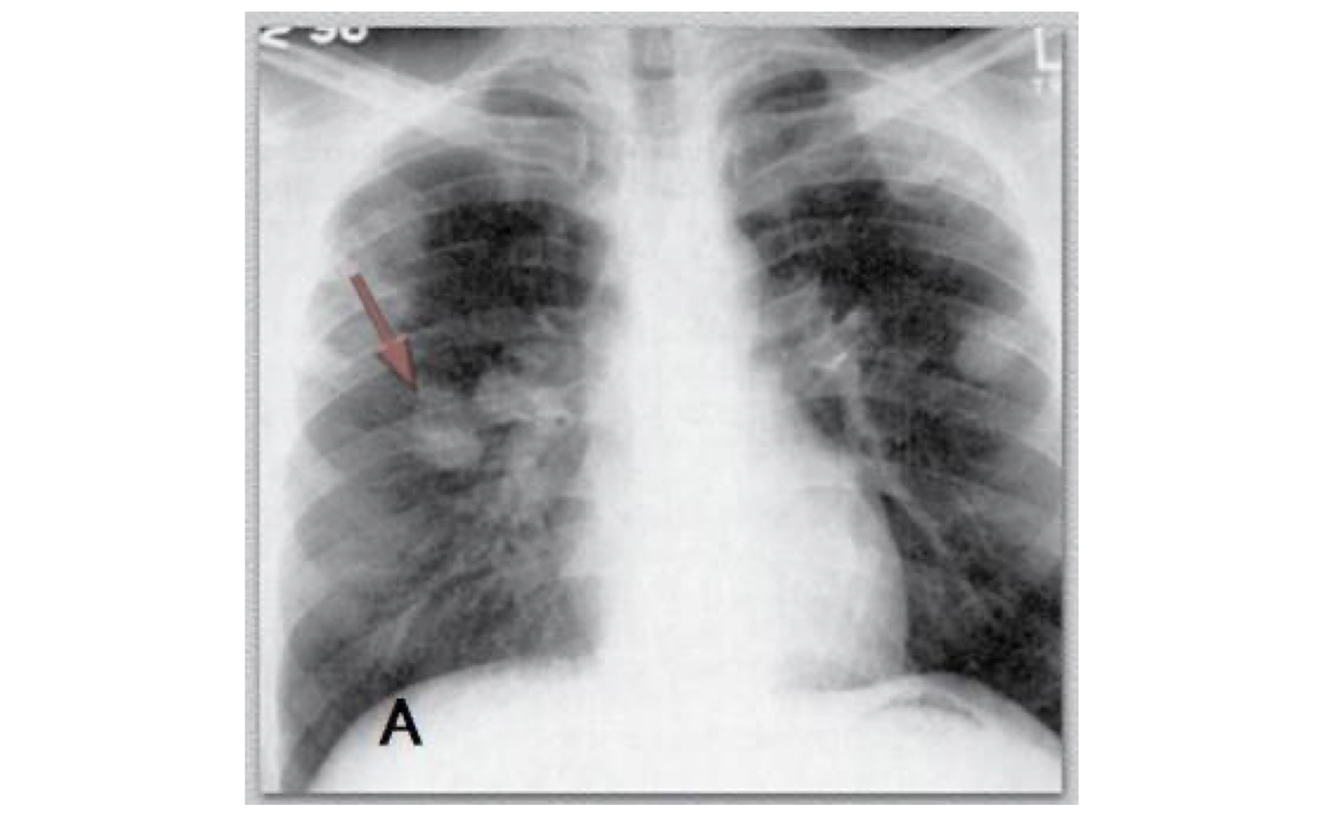

Qual a forma de TB demonstrada nesse exame?

TB cavitária